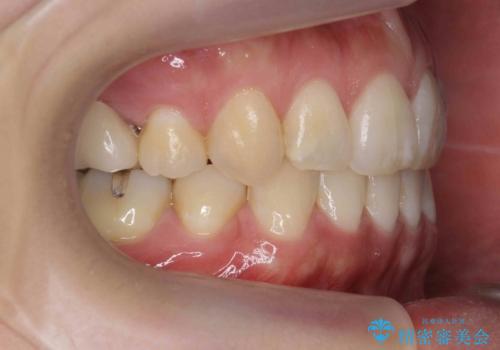

真ん中が右にずれている 前歯のがたつき 治療途中に地方へ引っ越したが、通ってワイヤー矯正

- 前歯のがたつきを主訴に来院。

前歯のクロスバイト、上の前歯の正中が右にずれていました。

右上の奥歯の高さもない状態でしたが、矯正治療が終わってからしっかりかぶせました。

上下左右の小臼歯を抜歯しています。

治療の後半に地方に転居され、2か月に一回の調整となり結果、治療期間がかかりました。

通院はしっかりしていただいたため、無事終了することができました。